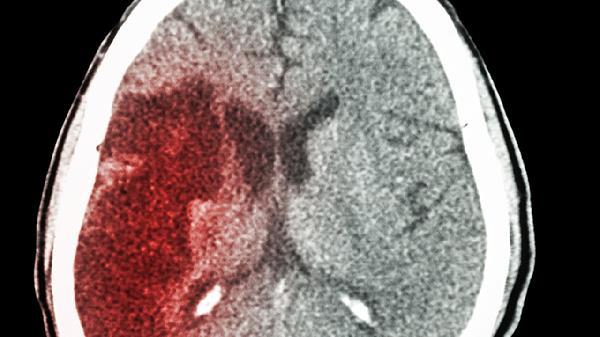

脑供血不足,可能会有这几个症状!预防脑梗,建议做好这几件事!

脑供血不足就像身体里的“交通堵塞”,看似不起眼却暗藏风险。你是否经常头晕眼花、记性变差?这些可能是大脑发出的“求.救信号”。别等到血管彻底堵住才后悔,这些预警信号和预防措施现在知道还不晚!